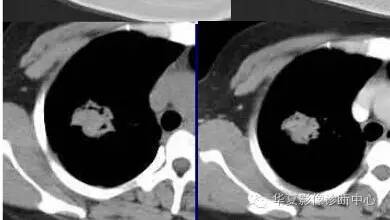

内带强化带,边界清楚

但是这个其实整体看起来不是分叶征

只是一个一个的凸起

磨玻璃结节良恶性影像分析策略磨玻璃结节良恶性影像分析策略 这个按常规看到血管由凹陷处进去常规95%考虑癌,可是这里却不是

除非说这里GGO边缘稍模糊一些

宽基底与胸膜相连

近端有模糊的高密度影